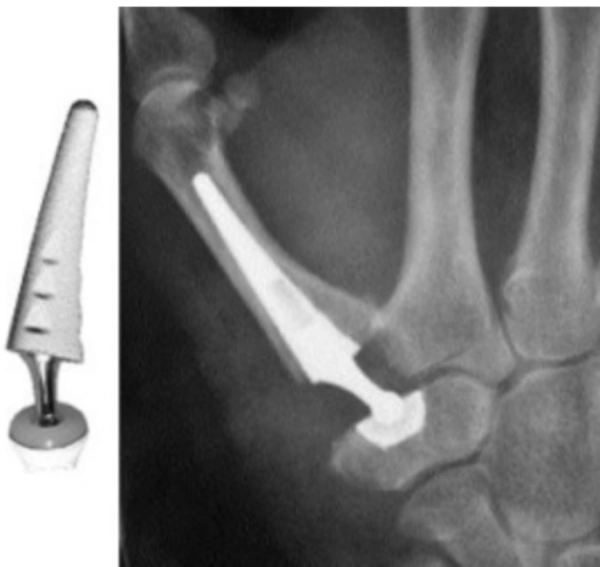

Prótesis trapeciometacarpiana

La artrosis trapeciometacarpiana (TMC) es la patología quirúrgica más frecuente en cirugía de la mano. La prevalencia de artrosis trapeciometacarpiana se ha establecido entre un 8-12%, llegando hasta un 33% en las mujeres postmenopáusicas.

Es la segunda localización de artrosis más frecuente en la mano, tras la articulación interfalángica distal. En la población general, una de cada cuatro mujeres y uno de cada doce hombres, presentan cambios degenerativos a nivel TMC, siendo la gran mayoría de ellos asintomáticos.

El tratamiento de la rizartrosis sintomática es muy amplio y varía desde diversas opciones de tratamiento conservador hasta la cirugía. Existen numerosos tratamientos quirúrgicos específicos para la artrosis TMC: trapecectomía con o sin tenosuspensión, artroplastias de interposición, artrodesis de la articulación o la sustitución protésica, que ha ganado importancia en los últimos años. El tipo de técnica empleada dependerá de la edad del paciente, actividad que desarrolla, estadio radiológico y la experiencia del cirujano.

La artroplastia trapeciometacarpiana lleva utilizándose desde hace décadas, aunque en los últimos años ha tenido un importante crecimiento, dado que es capaz de alcanzar un control del dolor prácticamente completo, mantener una fuerza importante y sobre todo, con buena movilidad.